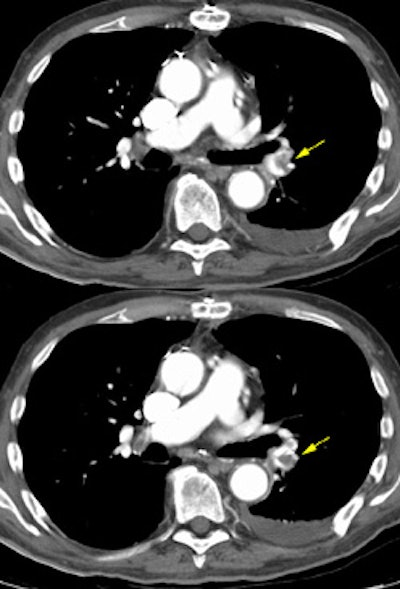

The example below demonstrates a pulmonary embolism in the left lower lobe pulmonary artery (Yellow arrows). Due to venous enhancement, clot can be seen within the right common femoral vein (Yellow arrow). The peripheral venous enhancement on this image obtained 3 minutes following intiation of the contrast infusion was approximately 90HU. The clot had an HU measurement of 44. (Click to view larger images if desired)